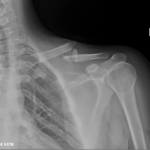

- Shoulder Fractures.

- Clavicle Fractures.